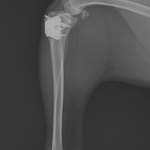

膝蓋骨内方脱臼+前十字靭帯断裂 PGR#21+CBLO #251

過去に膝蓋骨内方脱臼G4で手術を受けている患者さんが、急に跛行を呈するようになったとの事。関節炎が顕著であり、前十字靭帯断裂の併発も疑われます。ファットパッドサイン陽性、脛骨圧迫試験陽性、脛骨ピボット圧迫試験陰性でした。大腿骨滑車のリプレイスメントとCBLOで対応しました。